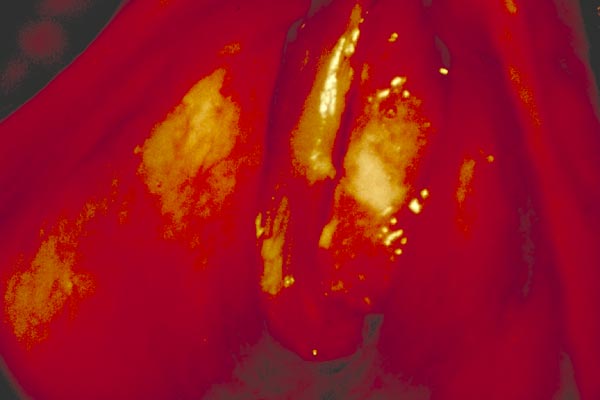

Bei älteren Patienten, die anamnestisch länger als 3 Wochen an Heiserkeit leiden, ist an ein Stimmbandkarzinom zu denken.

Stimmbandkarzinom